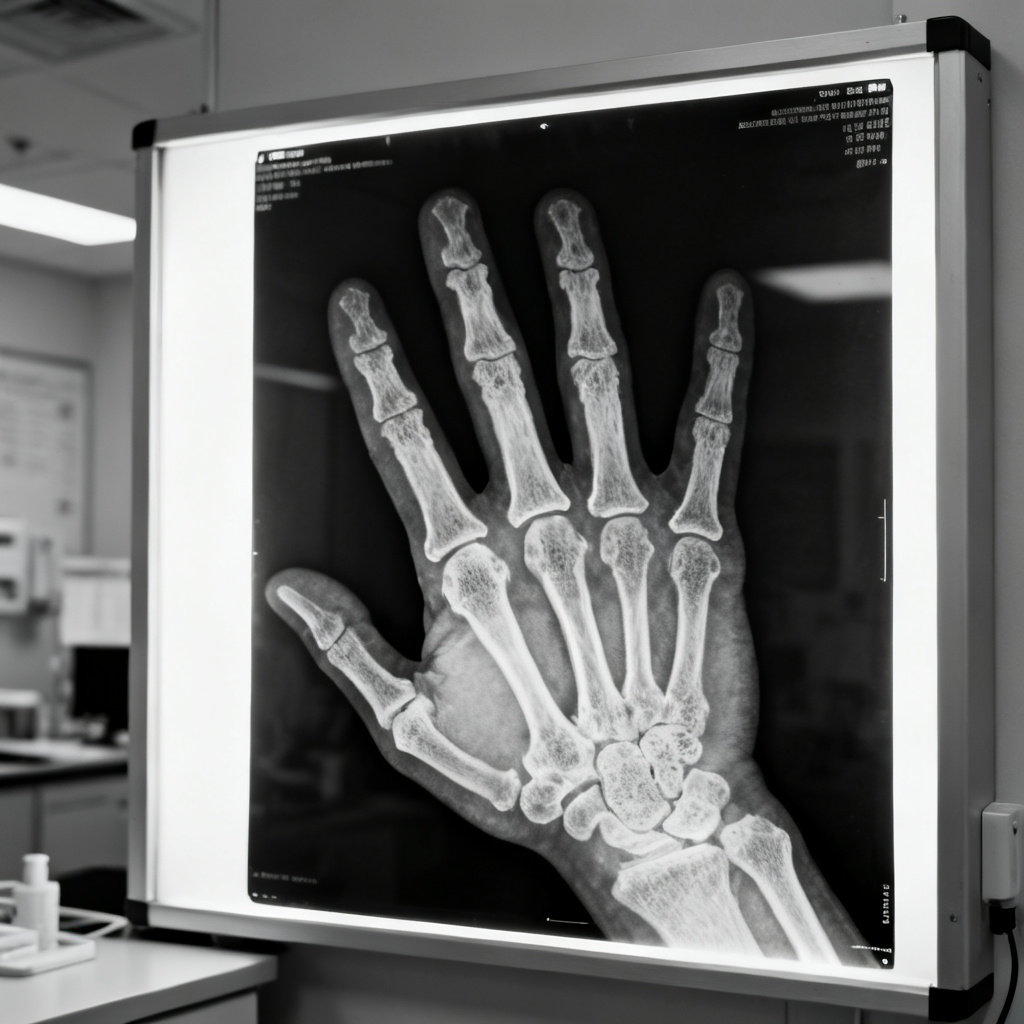

It's a special kind of light that doctors use to see inside your body, especially to check if your bones are broken or healthy.

一种能量很强的光线,可以穿过皮肤、肌肉等软组织,但很难穿过骨头等硬组织,所以被医生用来检查我们身体内部的情况,特别是看骨头有没有受伤、断裂。

After I fell off my bike, the doctor took an

X-ray

of my arm to make sure nothing was broken.

我从自行车上摔下来后,医生给我的胳膊拍了张**X光**,以确保没有骨折。

1895年的一天,德国物理学家伦琴的实验室里,一张放在射线管附近的底片竟离奇地自己变黑了,上面还隐约映出一把钥匙的轮廓。这绝对不该发生!当他试着把手放到射线前,惊恐的一幕出现了:屏幕上清晰显示的不是血肉,而是自己手掌的骨架!他偶然间捕捉到了能穿透物体的‘不可见之光’。